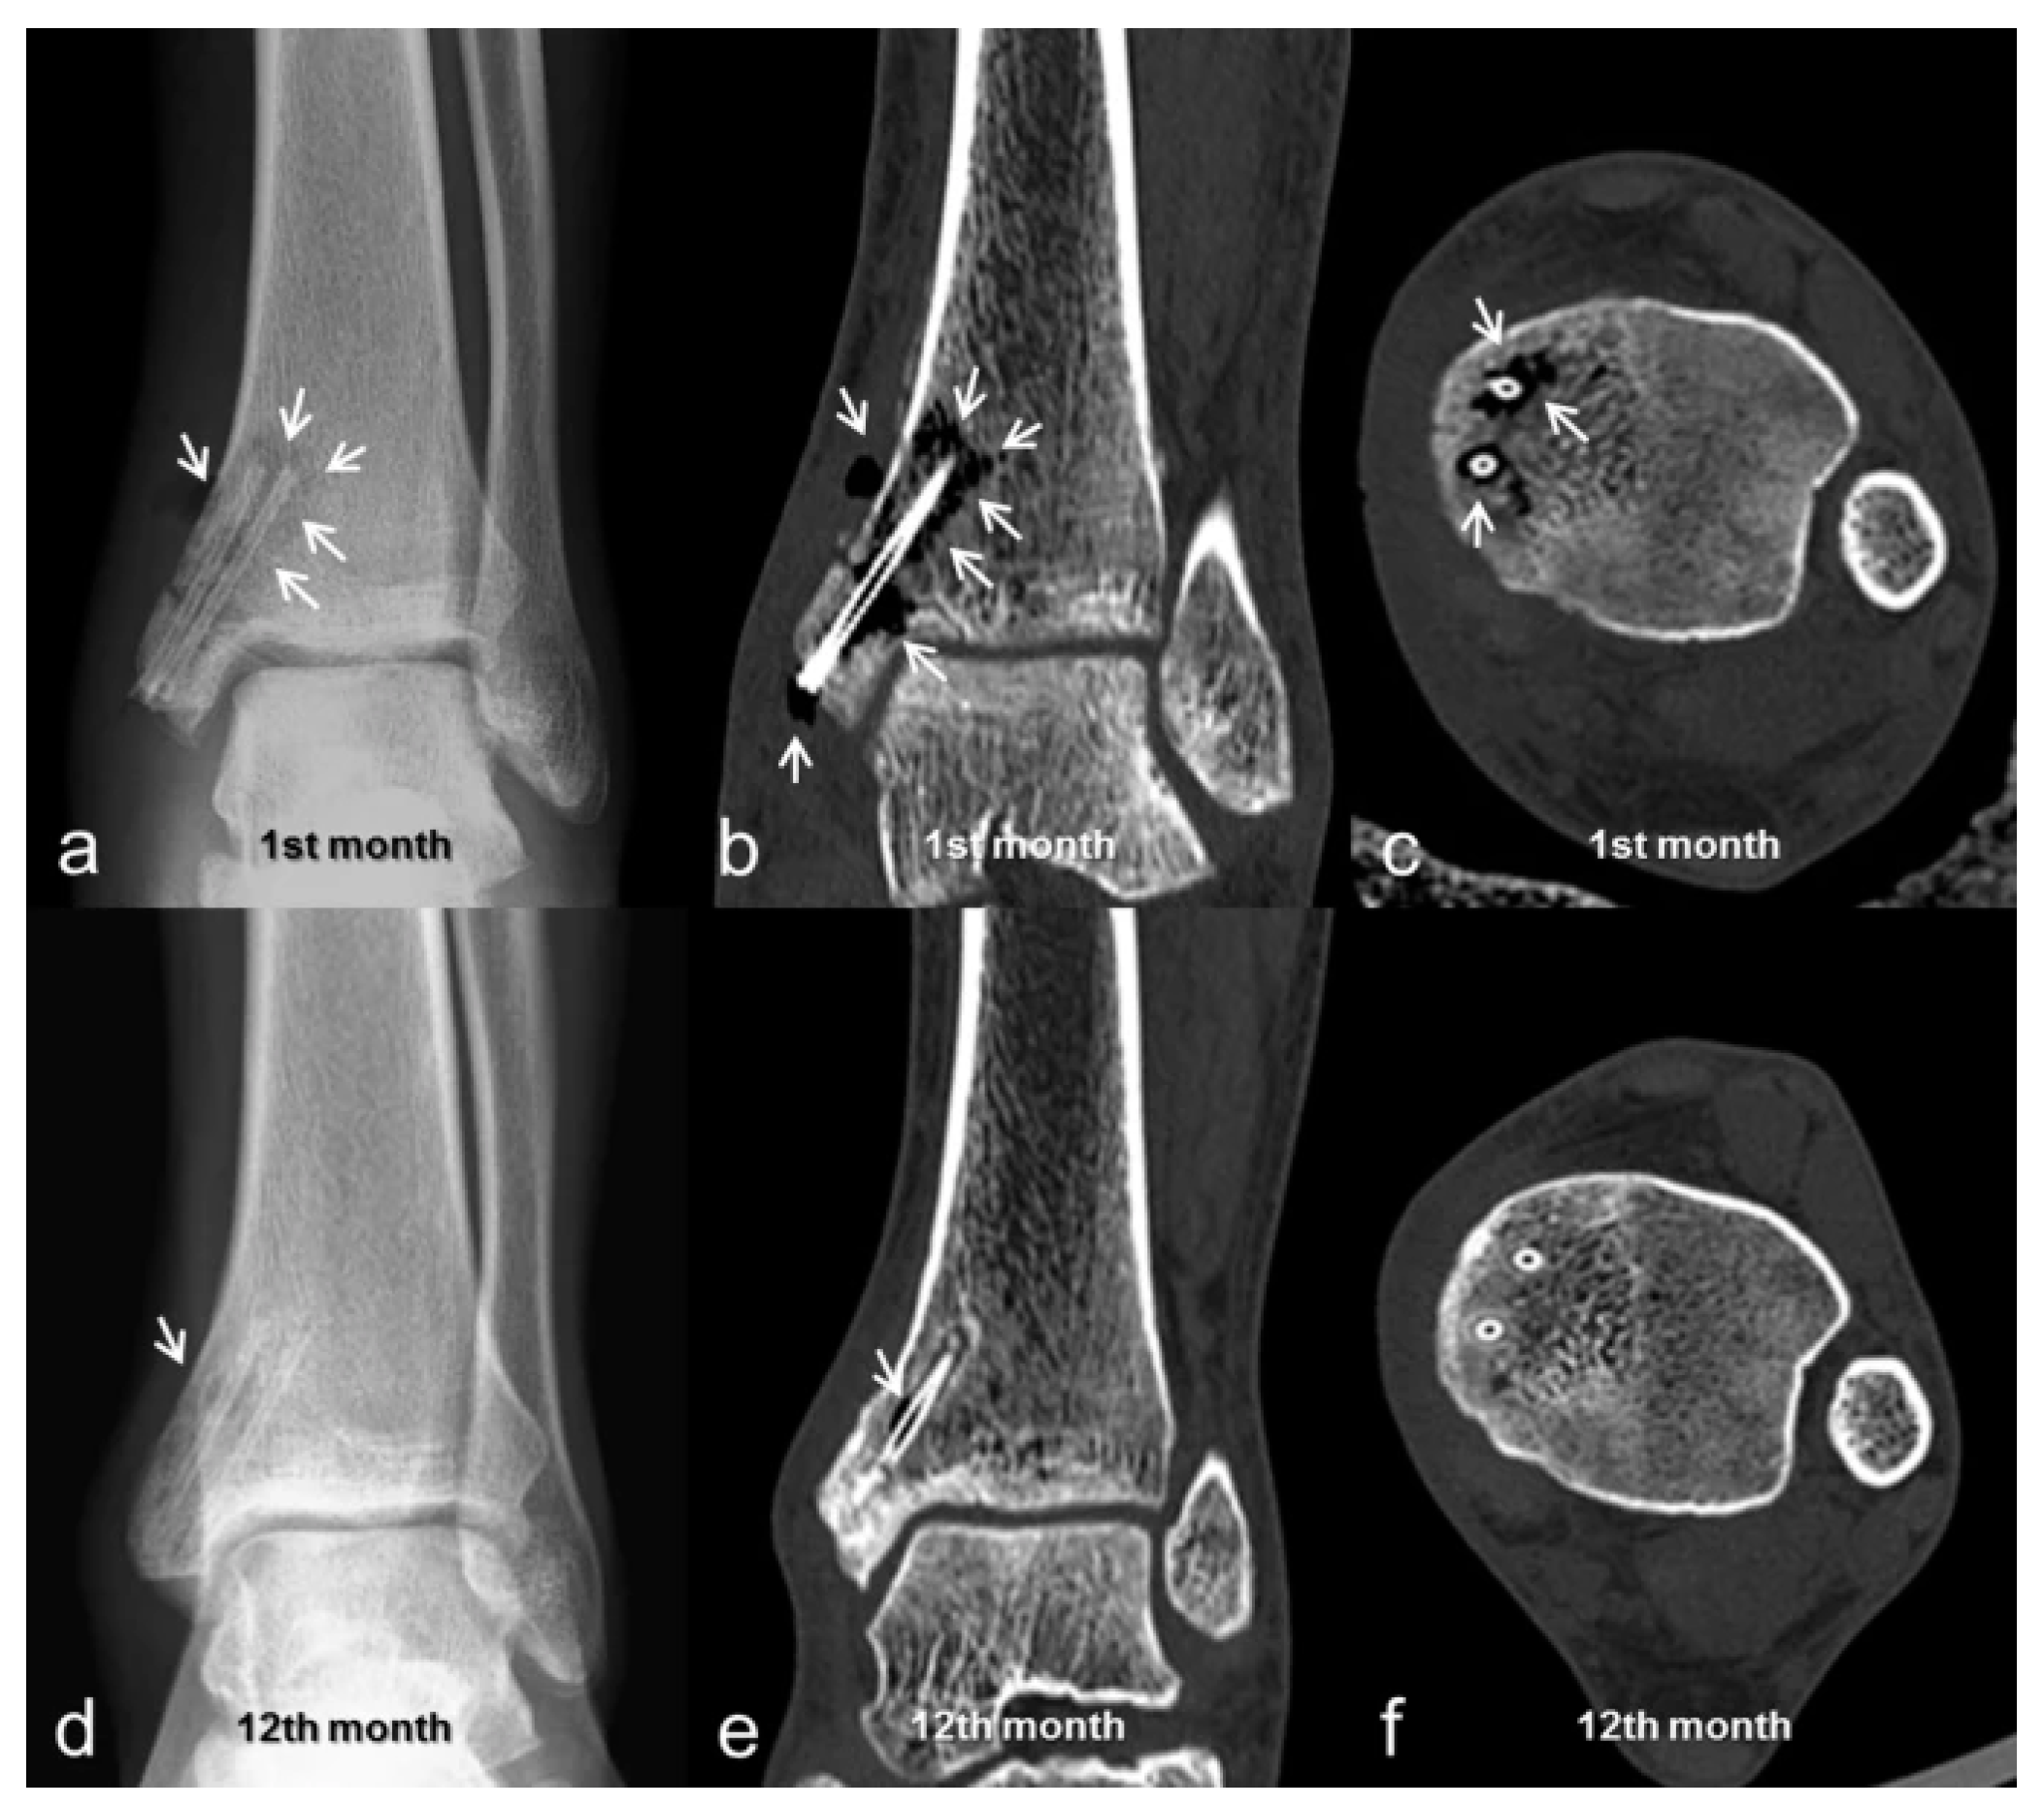

- May, H.; Alper Kati, Y.; Gumussuyu, G.; Yunus Emre, T.; Unal, M.; Kose, O. Bioabsorbable Magnesium Screw versus Conventional Titanium Screw Fixation for Medial Malleolar Fractures. J. Orthop. Traumatol. 2020, 21, 9. [Google Scholar] [CrossRef]